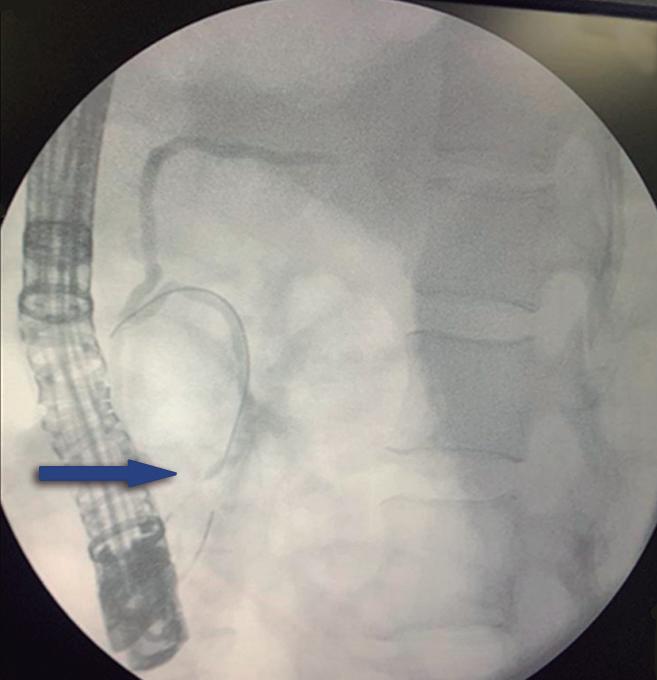

Conducto biliopancreático común largo

La unión entre el conducto colédoco y el conducto pancreático ocurre de diversas maneras, la mayoría son consideradas variantes normales y no tienen implicancias clínicas. Suelen confluir en un canal común con una longitud menor a los 5 mm y con un ángulo variable, alternativamente puede existir un ingreso al duodeno de ambos conductos por separado. En el canal común biliopancreático largo existe una unión precoz del colédoco con el conducto pancreático, con confluencia proximal al esfínter de Oddi por fuera de la pared duodenal. Para su diagnóstico se requiere una distancia mayor o igual a 15 mm entre la papila mayor y la confluencia de ambos conductos (Figura 6). Este conducto común largo permite el reflujo de las secreciones pancreáticas al colédoco, aumentando la presión intraductal y favoreciendo el desarrollo de quistes coledocianos. También favorece el reflujo de bilis hacia el conducto pancreático y, como consecuencia, predispone a la PA y PAR. 14,15

La flecha blanca señala la unión precoz del conducto colédoco con el conducto pancreático principal, alejada de la pared duodenal - papila mayor (cabeza de flecha), conformando un conducto biliopancreático común largo (> 15 mm).

A) Colangio-RM. La flecha señala la unión precoz del conducto colédoco con el conducto de Wirsung, alejado de la pared duodenal, conformando un conducto biliopancreático común largo. Se observa, como complicación, el desarrollo de un quiste de colédoco (cabezas de flecha). B) Colangio-RM magnificada. Medición de la distancia entre la pared duodenal, en el sitio de la papila mayor y la unión de los conductos colédoco y pancreático. C) Resonancia magnética, secuencia T1 con gadolinio, plano coronal. Unión de los conductos (flecha). Pared duodenal - papila mayor (cabeza de flecha).